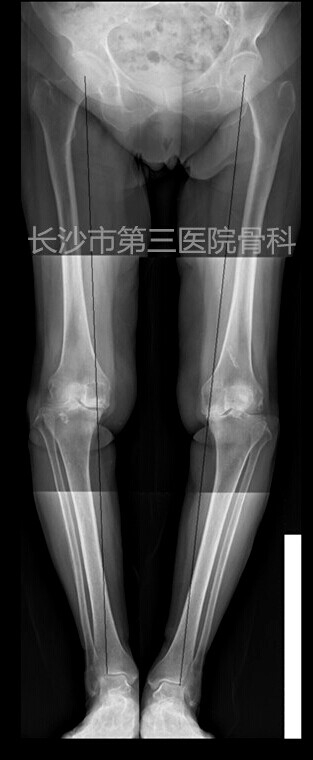

患者李某,女性,76岁。因反复右膝肿痛、活动受限10年,加重4天入院。体查:右膝内翻畸形,屈90度,伸10度,内侧关节间隙及髌骨上缘压痛,侧方应力试验阴性,肌力正常。诊断“右膝骨性关节炎”,为人工全膝关节置换适应症。

术前平片: